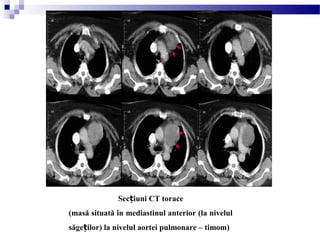

Sec iuniț CT torace

(masă situată în mediastinul anterior (la nivelul

săge ilor) la nivelul aortei pulmonare – timomț )